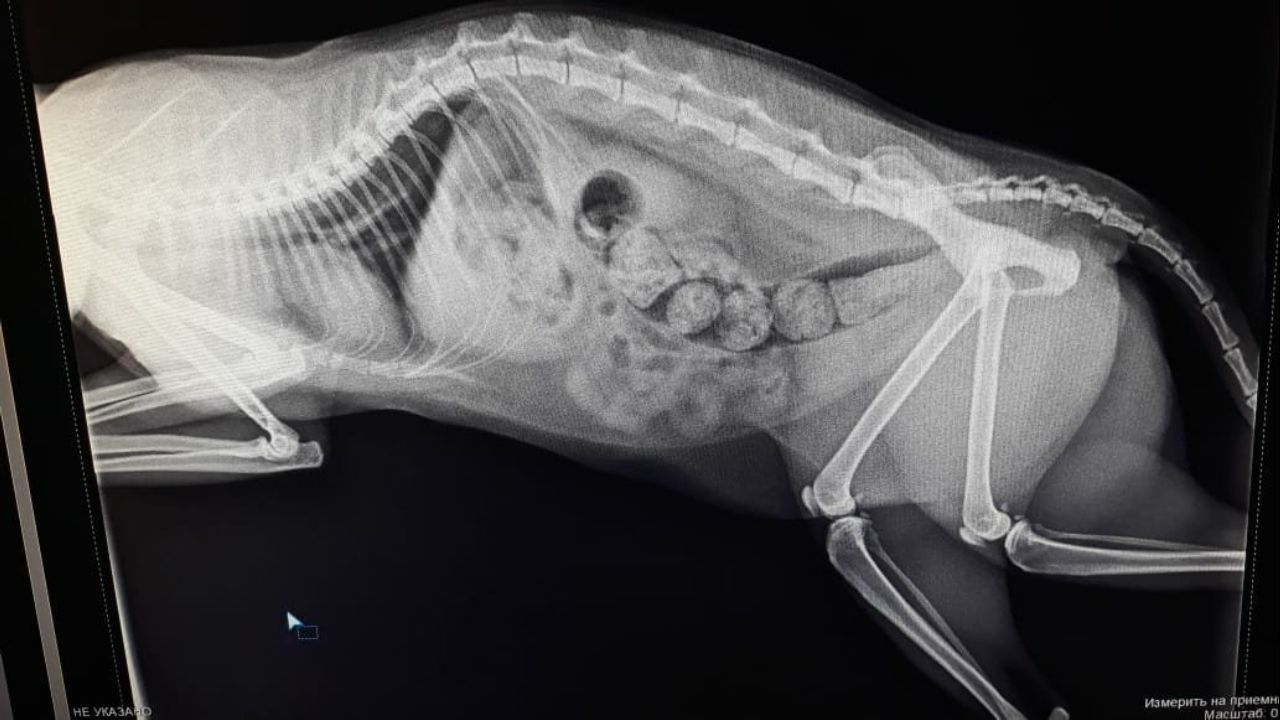

Цифровой рентген

Цифровой рентген кота или собаки с большой долей достоверности и информативности показывает состояние здоровья костей, суставов, легких, сердца, желудочно-кишечного тракта. Рентгенограмма передает структурные особенности исследуемых органов. Рентген позволяет диагностировать различные патологии. Ветеринарные специалисты назначают рентген кошек и собак для оценки состояния здоровья костной и мышечной системы, в частности, при переломе костей, дисплазии тазобедренного сустава, артрите у кошек или собак. Рентгенография также используется для исследования внутренних органов, включая сердце, легкие, печень, почки, кишечник, желудок. Позволяет обнаружить инородное тело, находящегося в желудке или кишечнике, а также наличия жидкости, опухоли.

Рентген для собак и кошек часто используются в сочетании с ультразвуком для более детальной диагностики состояния здоровья домашних животных. Рентгенография животных назначается:

Если животное травмировалось, рентген костно-суставной системы позволит оценить степень тяжести повреждений (перелом, трещина), а также детально рассмотреть участок повреждения, увидеть осколки, если травма тяжелая. Для врача это важные и необходимые сведения, позволяющие назначить оптимальную схему лечения. Рентген лап собаки или кошки позволяет правильно и своевременно спланировать лечение, цена его при этом невелика.

Для выявления новообразований.

Если животное долго не опорожняется, возможно, это связано с непроходимостью кишечника.

При симптомах сердечно-сосудистых заболеваний.

При непрекращающемся кашле у животного рентген легких кошки или собаки позволяет диагностировать пневмонию или застрявший инородный предмет в дыхательных путях.